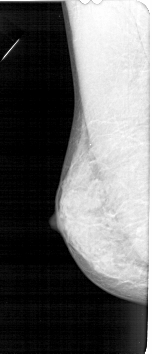

A_1352_1.RIGHT_MLO

LEFT_MLO LINES 5296 PIXELS_PER_LINE 2266 BITS_PER_PIXEL 12 RESOLUTION 43.5 NON_OVERLAY